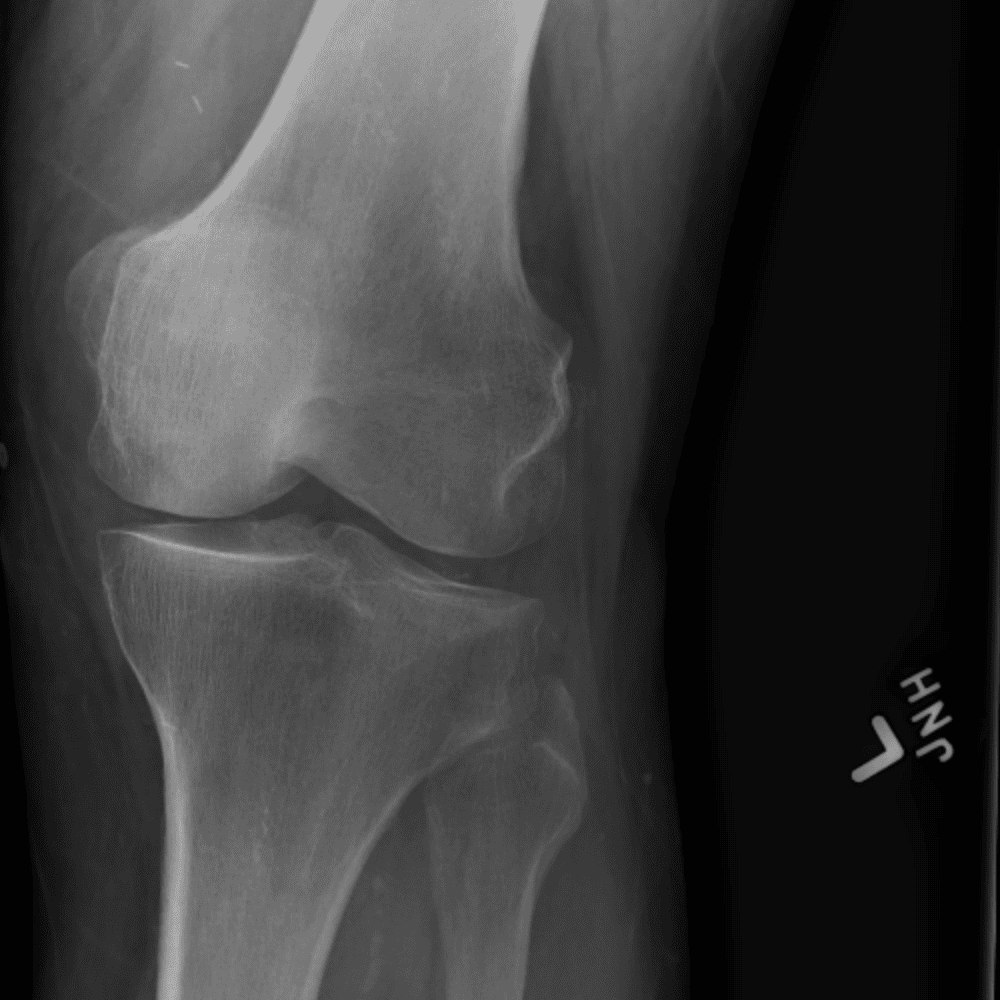

Simula o plantão incluindo casos sutis ou difíceis e alguns normais.